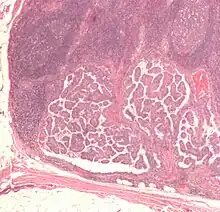

Cut surface of a liver showing multiple paler metastatic nodules originating from pancreatic cancer